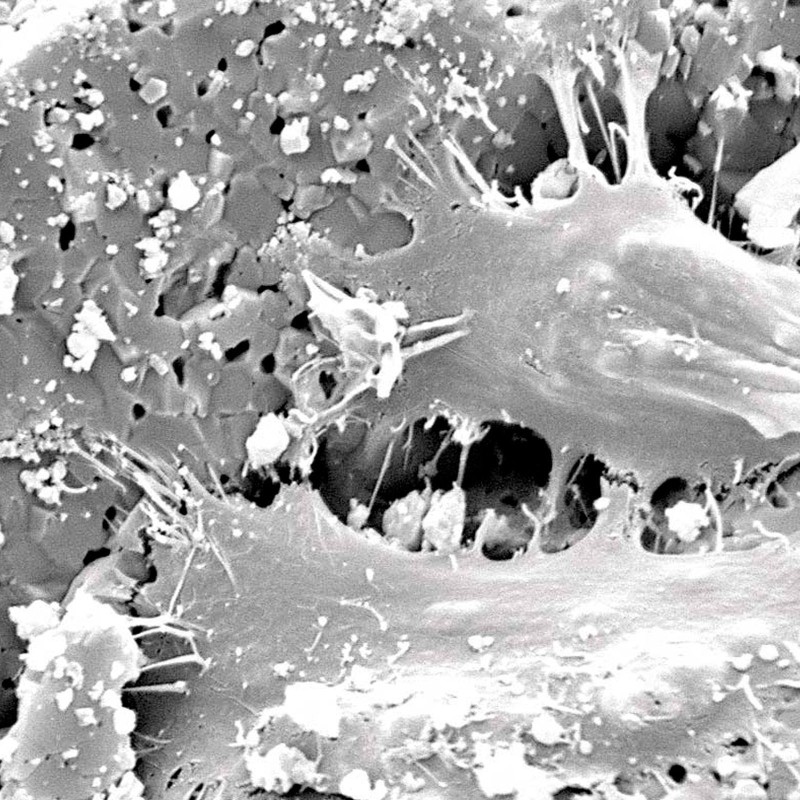

Porosidad interconectada ultra alta

La osteoconductividad de maxresorb ® se basa en una red de poros interconectados, una porosidad total muy alta de aprox. 80% así como su superficie muy rugosa 3, 4, 5 . La superficie nanoestructurada facilita la adsorción de sangre, proteínas y células madre y promueve la diferenciación celular y la integración ósea. maxresorb ® es, por lo tanto, un andamio ideal para la migración de células formadoras de hueso y la unión de moléculas de señalización, que pueden acelerar la integración y regeneración del tejido 6, 7 .

Para dejar espacio para el proceso regenerativo, sólo se recomienda una compresión suave de las partículas. Permite la revascularización y osteointegración de las partículas del injerto óseo mediante la red de poros tridimensionales de maxresorb ® .